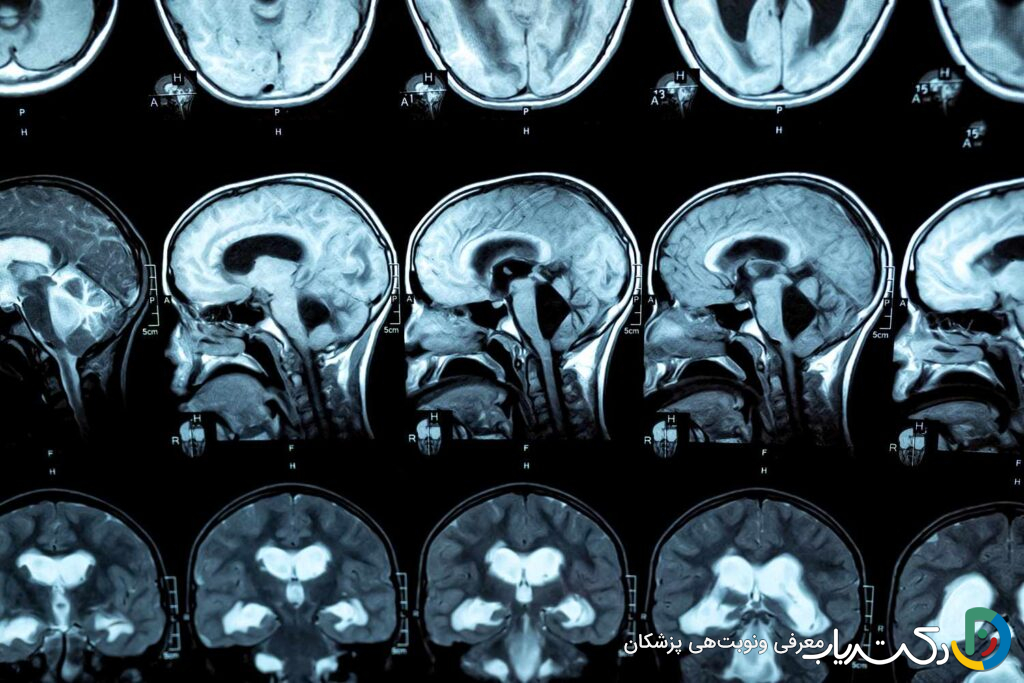

• تشخیص دقیق حیاتی است: تصویربرداری پیشرفته مغز (MRI و سونوگرافی) و در موارد مشکوک، مشاوره و آزمایش ژنتیک، برای تعیین علت دقیق و برنامه‌ریزی بهترین استراتژی درمانی ضروری است.

تصویربرداری از مغز برای تأیید قطعی تشخیص، شناسایی علت زمینه‌ای (مانند انسداد) و تعیین شدت هیدروسفالی کاملاً ضروری است.

• سونوگرافی جمجمه: یک روش ایمن، غیرتهاجمی و سریع برای نوزادان است که می‌توان از طریق ملاج باز آن‌ها انجام داد. این روش به خوبی اندازه بطن‌های گشادشده را نشان می‌دهد و برای غربالگری اولیه و پیگیری پس از درمان بسیار مفید است. سونوگرافی در دوران بارداری (سونوگرافی پره‌ناتال) نیز می‌تواند هیدروسفالی را در جنین تشخیص دهد.

• تصویربرداری رزونانس مغناطیسی (MRI): این روش استاندارد طلایی برای تشخیص هیدروسفالی است. MRI بدون استفاده از اشعه ایکس، تصاویر بسیار دقیق و با جزئیات بالا از ساختار نرم مغز، بطن‌ها و مسیرهای جریان CSF ارائه می‌دهد. این روش می‌تواند علت دقیق انسداد (مانند تومور، کیست یا تنگی مجرا) را مشخص کرده و به جراح در برنامه‌ریزی بهترین روش درمانی کمک کند.

• توموگرافی کامپیوتری (CT Scan): سی‌تی اسکن سریع‌تر از MRI است و در شرایط اورژانسی (مانند ضربه به سر) برای ارزیابی سریع اندازه بطن‌ها و وجود خونریزی بسیار مفید است. با این حال، به دلیل استفاده از اشعه ایکس، برای پیگیری‌های مکرر در کودکان کمتر ترجیح داده می‌شود.